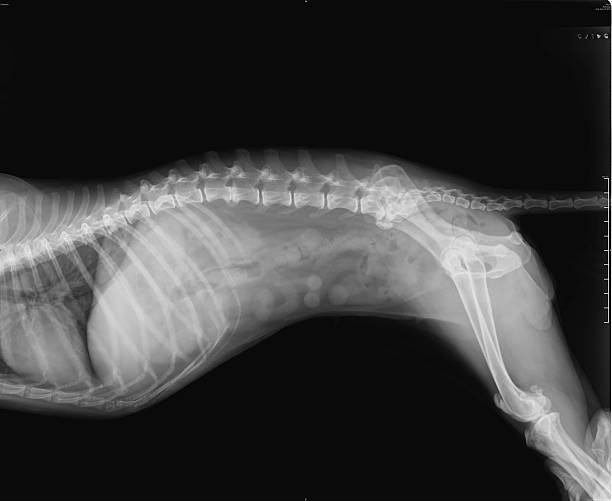

Os exames de raio x em cachorro em curitiba são fundamentais para a saúde, pois possibilitam aos veterinários diagnosticar diversas condições de saúde que não são visíveis a olho nu.

Seja para investigar uma possível lesão, identificar a presença de corpos estranhos ou acompanhar o desenvolvimento de uma doença, o raio x é uma ferramenta indispensável para o diagnóstico veterinário.